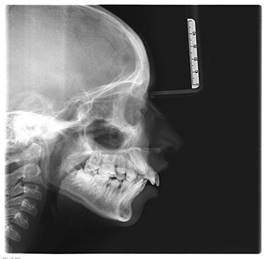

En la Cefalometría De Lavergne Y Petrovick, realizada tomando como referencia la radiografía lateral de cráneo (Figura 4) el paciente tiene: rotación mandibular neutra, maxilar mayor que la mandíbula, relación distal anteroposterior con relación vertical normal (R2DN)

Para ver la necesidad de espacio en los arcos superior e inferior, se realizaron los análisis de Pont (espacio transversal) en el cual se obtuvo que el paciente presenta déficit de espacio tanto en la zona anterior como en la posterior en los dos arcos. En el análisis de Moyers (espacio para erupción de caninos y premolares), paciente presenta déficit de espacio solo en el arco inferior.

Con el estudio de la cefalometría se obtuvo que el paciente presenta:

-Perfil retrognático

-Retrognatismo mandibular

-Rotación mandibular en sentido de las manecillas del reloj

-Crecimiento vertical

-Clase II dental y esquelético

-Longitud mandibular corta

-Patrón dolicofacial

-Incisivos superiores proinclinados y protruidos

-Overjet y overbite aumentados

-Mordida profunda